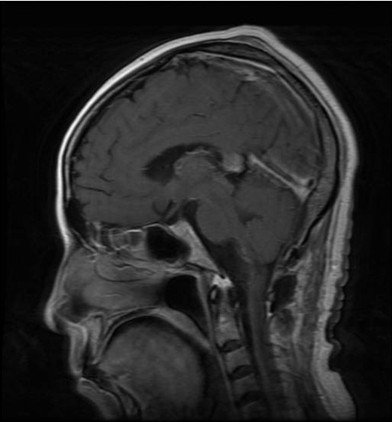

病例二:王**,男性,53岁。因做小脑肿瘤术后9年,头痛头晕,伴颈部疼痛、走路不稳半年入院。入院诊断:延颈交界血管网织细胞瘤。术式:后正中入路延颈交界区血管网织细胞瘤切除术。术后病理:血管网织细胞瘤。术后头痛头晕,颈部疼痛消失,走路平稳。

术前